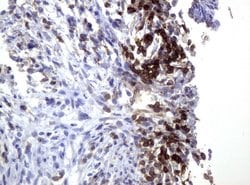

CD3 Mouse anti-Human, Clone: UMAB54, liquid, UltraMAB™

Mouse Monoclonal Antibody

Brand: Origene Technologies UM500048

CD3 epsilon is part of the CD3 subunit complex which is crucial in transducing antigen-recognition signals into the cytoplasm of T cells and in regulating the cell surface expression of the TCR complex. T cell activation through the antigen receptor (TCR) involves the cytoplasmic tails of the CD3 subunits CD3 gamma, CD3 delta, CD3 epsilon and CD3 zeta. These CD3 subunits are structurally related members of the immunoglobulins super family encoded by closely linked genes on human chromosome 11. The CD3 components have long cytoplasmic tails that associate with cytoplasmic signal transduction molecules and this association is mediated at least in part by a double tyrosine-based motif present in a single copy in the CD3 subunits. CD3 may play a role in TCR-induced growth arrest, cell survival and proliferation. The CD3 antigen is present on 68-82% of normal peripheral blood lymphocytes, 65-85% of thymocytes and Purkinje cells in the cerebellum. It is never expressed on B or NK cells. Decreased percentages of T lymphocytes may be observed in some autoimmune diseases. The genes encoding the CD3 epsilon, gamma and delta polypeptides are located on chromosome 11. Defects in this gene are associated with T cell immunodeficiency and has been linked to Type 1 Diabetes deficiency in women.Specifications

| Immunocytochemistry, Immunofluorescence, Immunohistochemistry (Paraffin) | |

| UMAB54 | |

| Full length human recombit protein of human CD3E produced in HEK293T cell. | |